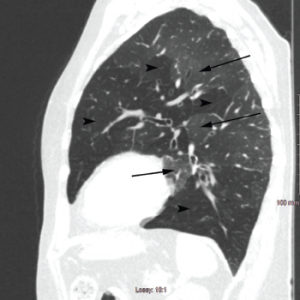

Figure 2b: Sagittal Section

Arrowheads indicate areas of hyperlucency, suggesting air trapping, compared with hypolucent areas, indicated by arrows.

Chest radiography typically reveals clear lungs, often with hyperinflation, but HRCT of the chest is the diagnostic imaging modality of choice. Classic HRCT findings of OB-RA are mosaic attenuation and hyperinflation. Mosaic attenuation is defined as patchy areas of hyperlucency due to air trapping from bronchiolar obstruction and is best recognized during expiration (e.g., dynamic phase HRCT). Other common HRCT findings are bronchial wall thickening, cylindrical bronchiectasis and centrilobular pulmonary nodules.12